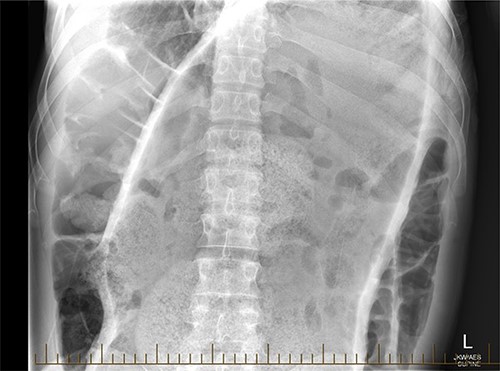

A 28-year-old gentleman self-presented to the emergency department with profuse overflow diarrhea and vomiting. The patient reported he had normal bowel motion until the morning of presentation. He denied any abdominal pain. On examination, the patient appeared pale, diaphoretic and dehydrated. His abdomen was grossly distended, however, was nontender. He was afebrile yet experienced sustained sinus tachycardia to a rate of 120 beats per minute. His blood pressure sat at 96/75 mmHg and was tachypneic to a respiratory rate of 30 and was saturating at 96% on room air. His blood tests showed a leukocytosis to 31, severe metabolic acidosis pH 7.18, lactate 7.7 and hyperkalemia K 6.0 estimated glomerular filtration rate (eGFR) of 68 mL/min/1.73 m2 and a creatinine count of 125μmol/L The computed tomography imaging of his abdomen revealed a massively dilated rectum and sigmoid colon extending to his splenic flexure without evidence of a perforation (Figs 1 and 2). Plain film radiography shows a sizeable faecaloma in the sigmoid colon (Fig. 3).